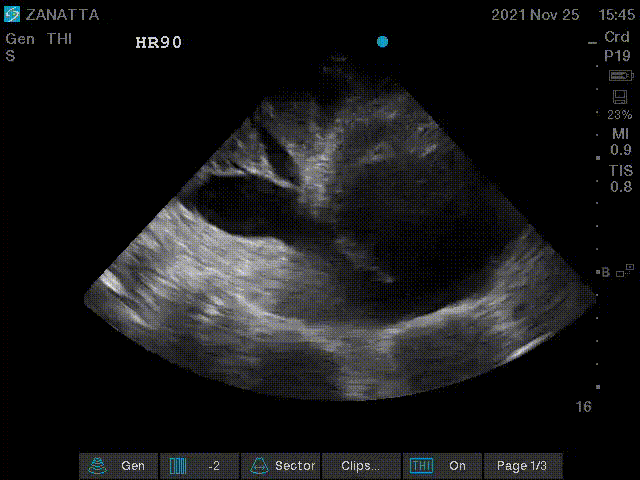

Next, you obtain an apical four chamber view and measure the TAPSE.

Apical Four Chamber

- RV enlargement is defined by RV size (at the tricuspid annulus) >⅔ the size of the LV (at the mitral annulus) severe is defined by RV size > LV size

- RV pressure overload is defined by septal flattening in systole and RV volume overload is defined by septal flattening in diastole